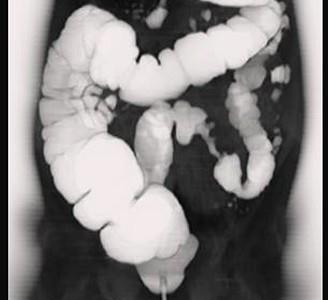

问题 女,56岁,腹胀、腹痛、左下腹包块三月余,无肛门排气,影像检查如图,最可能的诊断是 ( )

选项 A、乙状结肠淋巴瘤 B、乙状结肠息肉 C、乙状结肠结核 D、乙状结肠腺癌 E、乙状结肠crohn病

答案 D